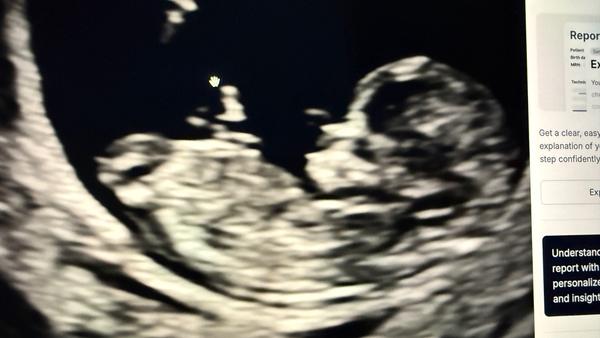

Může někdo určit pohlaví podle ultrazvuku ve 13+3 týdnu?

Prosím co by jste řekli u mě? 😁

@markeetaaa24 kluk. To pod pupečníkem trčí nahoru 😉